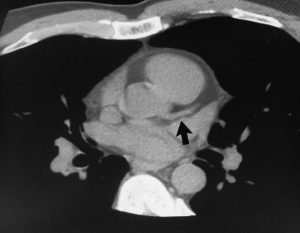

Severe Calcification